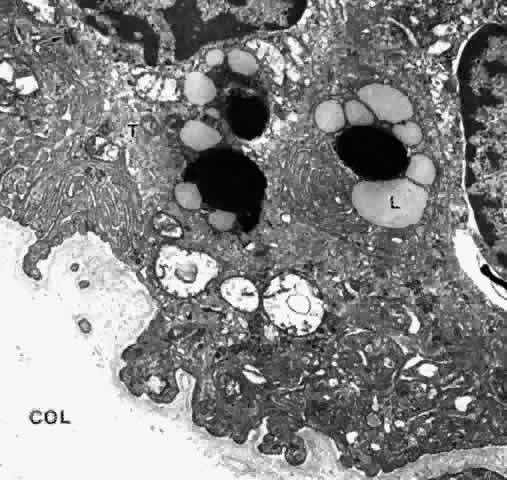

The cytoplasm of the PE cell is more electron-dense than that of the NPE cell, containing many free ribosomes, actin filaments, and predominantly cytokeratin-containing intermediate filaments (Fig. 25).26 The mitochondria are smaller and fewer in number than in the NPE, as is the RER, and the Golgi apparatus is present irregularly. There are large numbers of rounded and some elliptical melanin pigment granules of the 0.8 μm to 2 μm size characteristic of neuroepithelium, and three to four times larger than those of the stromal pigment cells. A decrease in pigment granules occurs in the PE over the crests of the ciliary processes from the fourth decade of life. Lipid droplets and complex lipopigment granules are seen within the cytoplasm during aging (see Fig. 25). The base of the PE cell is markedly infolded, lying on a basement membrane that with aging develops a thick, multilaminar pattern generally denser than that over the NPE cells but also containing vesicular, fibrillar, and granular inclusions (Fig. 26). The basement membrane of the PE is often very close to or almost continuous with that of the fenestrated capillaries in the pars plicata region (Fig. 27).

Fig. 25. Ciliary pigmented epithelial cells in mid pars plana of a young adult. The cytoplasm is electron-dense with many tonofilaments (T) (intermediate filaments). Lipid droplets (L) are present around dark lysosomal residual bodies. Desmosomes connect the cells (arrow). The basal surface and intercellular junctional areas are markedly infolded, and the basement membrane is moderately thick. Negative images of collagen fibers (COL) are seen below, in the dense stroma typical of this region (X 17,500)